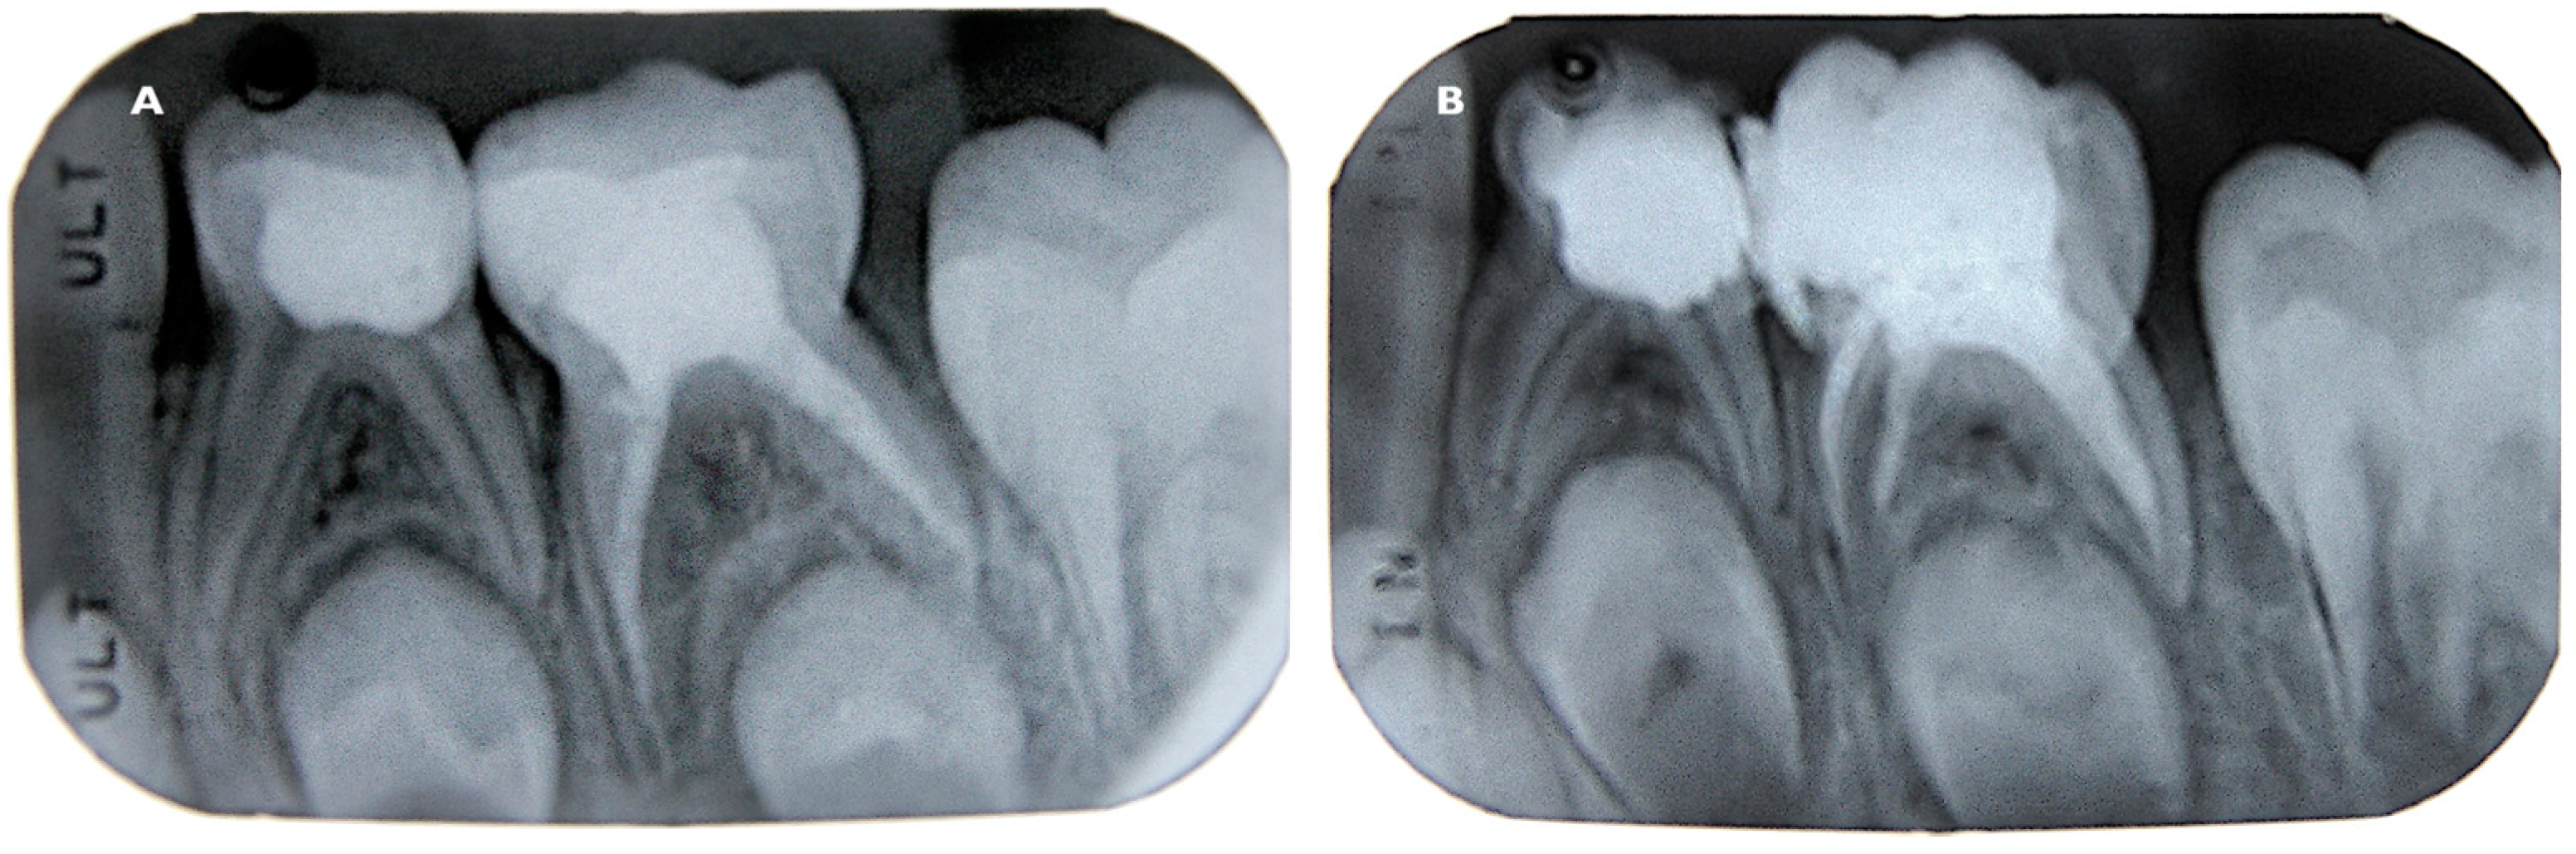

2. Materials and Methods

3. Results